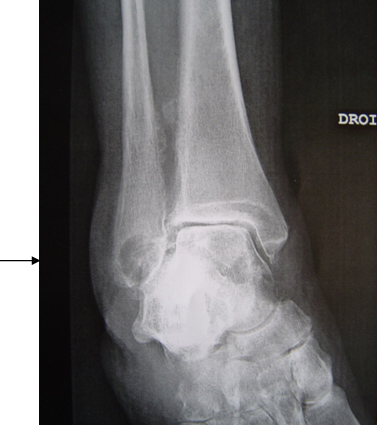

La radiographie standard ci-dessous montre un pincement tibio-talien, une ossification de la membrane inter-osseuse et surtout une géode volumineuse de la malléole de la fibula.